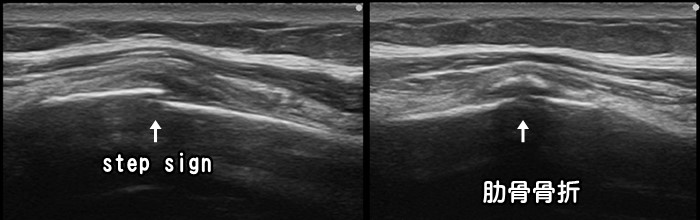

肋骨骨折

転倒などして脇腹を強打すると肋骨骨折を発症します。レントゲンでの肋骨骨折の診断率は40~60%と言われており2人に1人は見逃されてしまいます。一方、超音波検査では85%なのでレントゲンでは異常なしと言われても骨折を確認できる事が多々あります。ただし複数の肋骨が折れていたり、1本の肋骨が複数部位で折れている場合はCT検査などがおすすめです。